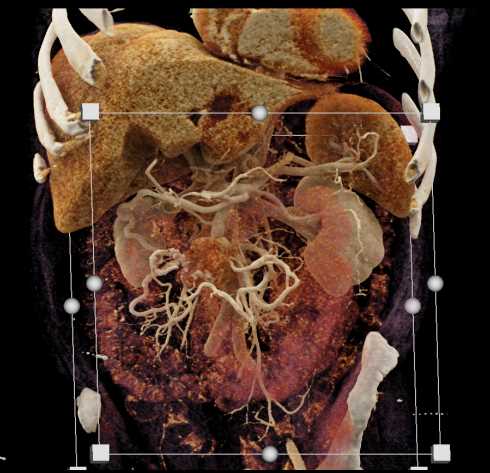

Carcinoid Tumor with Desmoplastic Reaction